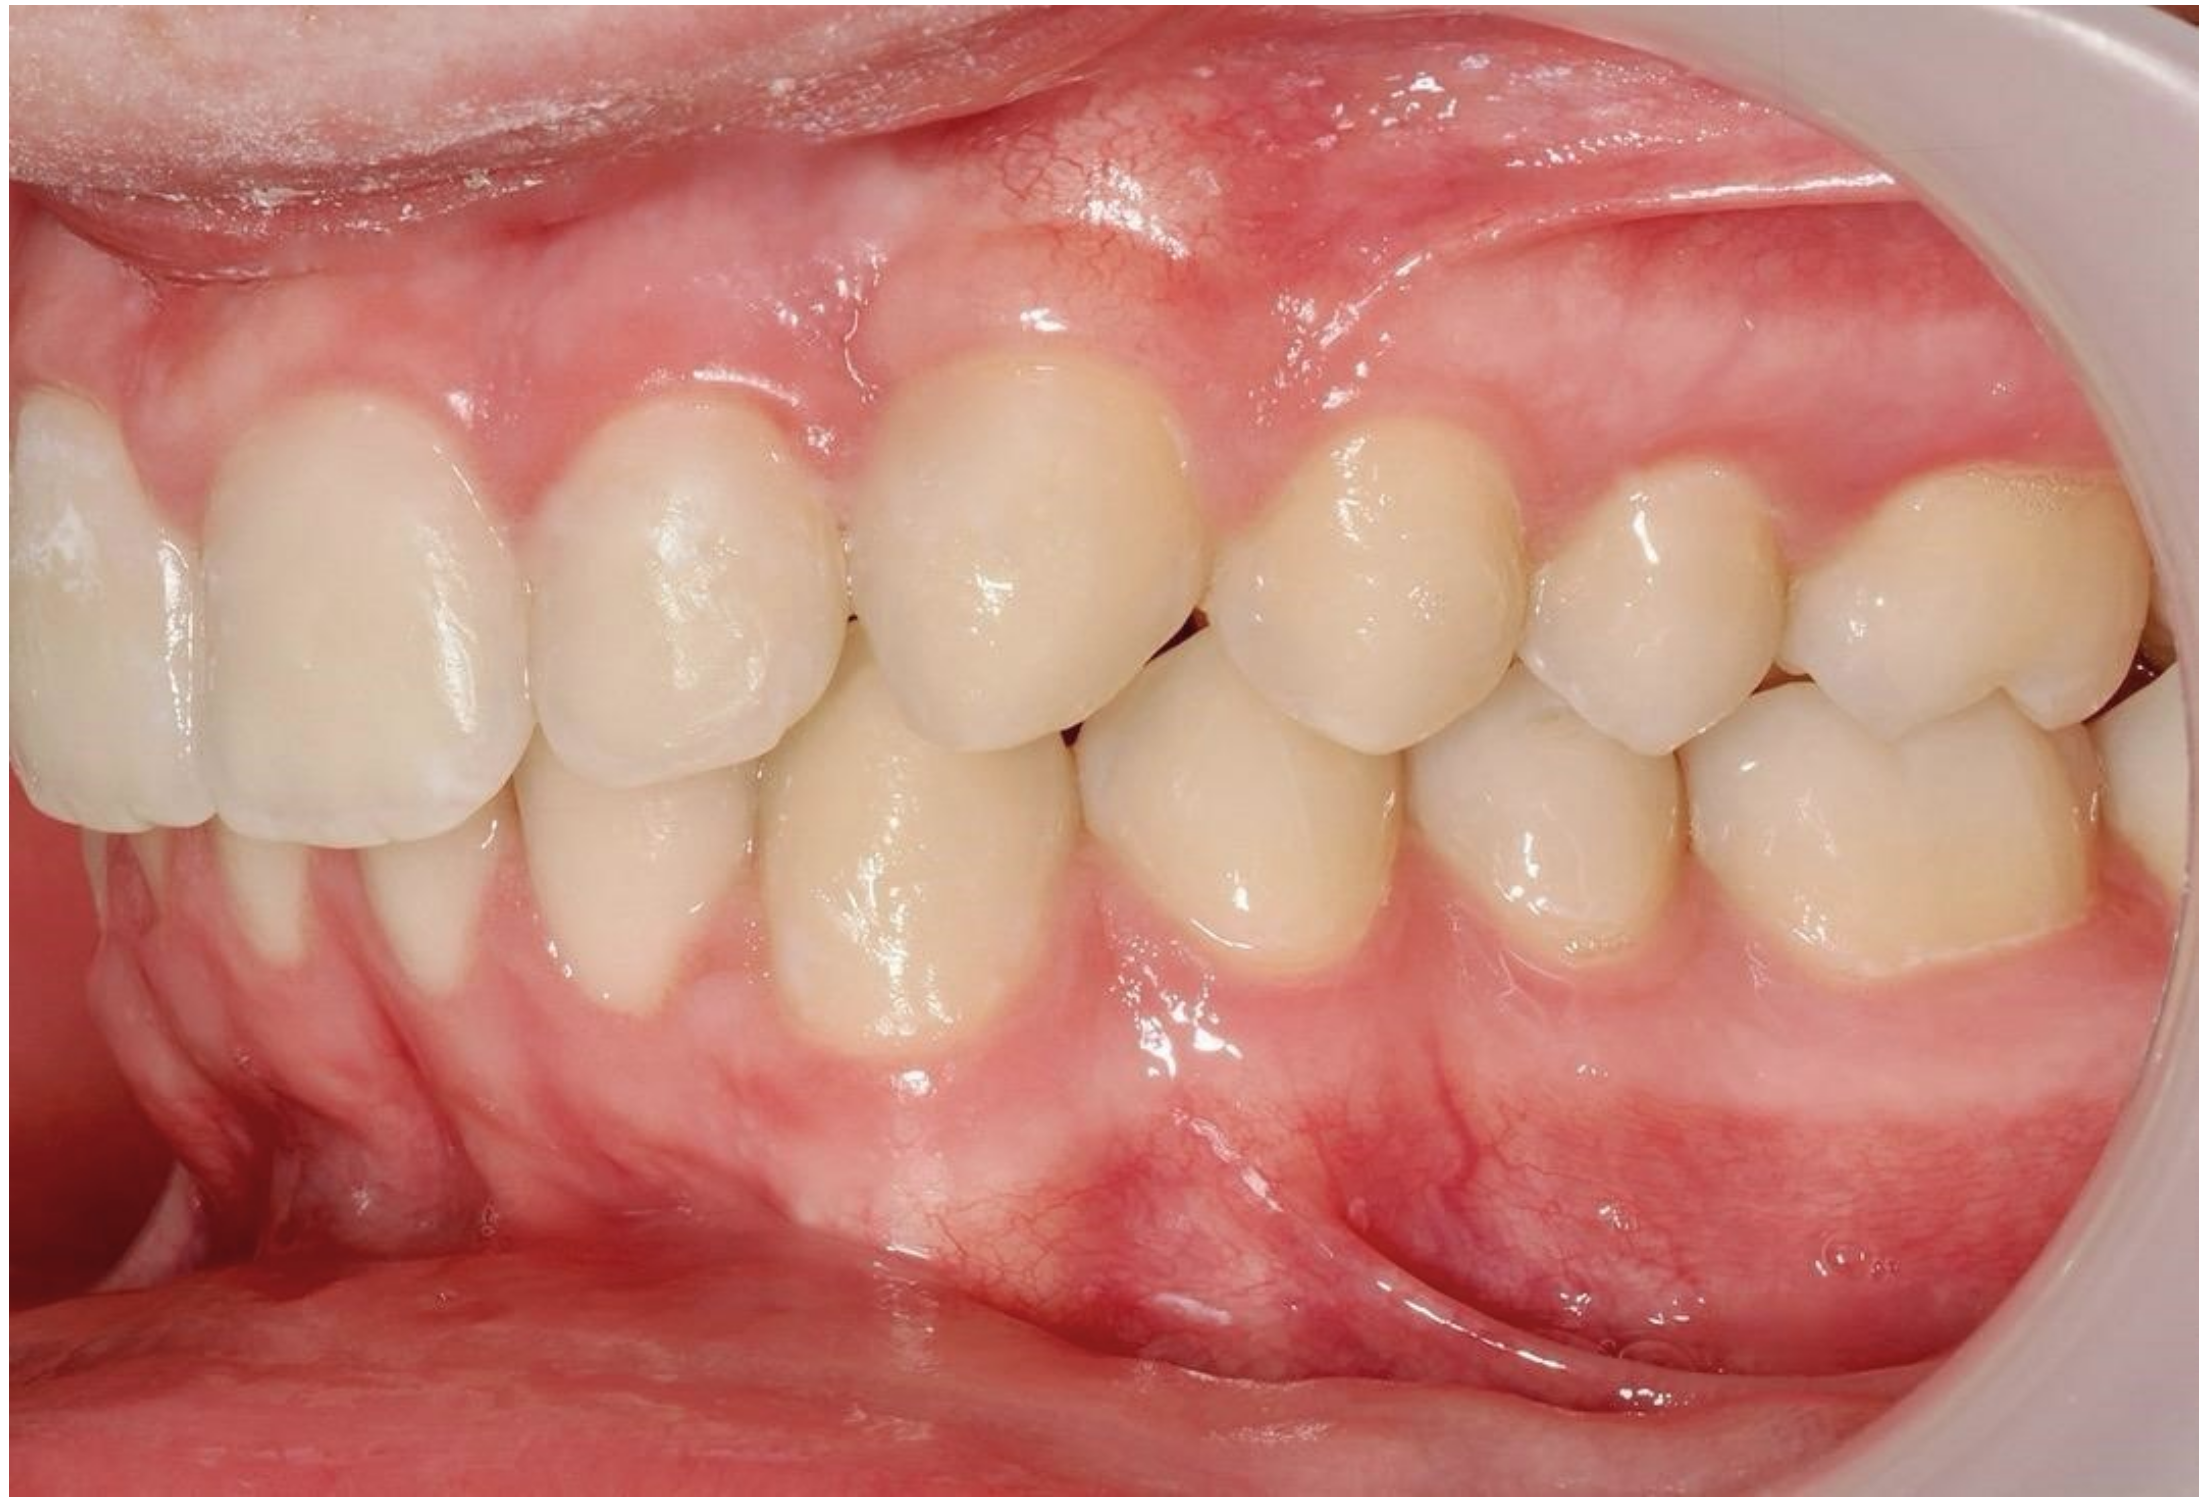

A 13-year-old male patient presented with Class II Division 2 malocclusion, a bilateral Class II sagittal relationship, and retroclined incisors. Cone-beam computed tomography revealed a palatally impacted maxillary left canine (tooth 23), with its cusp located palatally to the apical half of the left lateral incisor. The root exhibited significant apical curvature, extending toward the floor of the maxillary sinus (Figure 12 and Figure 13), making spontaneous eruption unlikely.

Figure 12.

Initial intraoral lateral photo.

Ultimately, after 30 months of treatment, canine 23 was successfully repositioned into the dental arch, achieving functional occlusion (Figure 23).

Figure 23.

Canine 23 properly positioned in the arch in occlusion; 30 months of treatment.